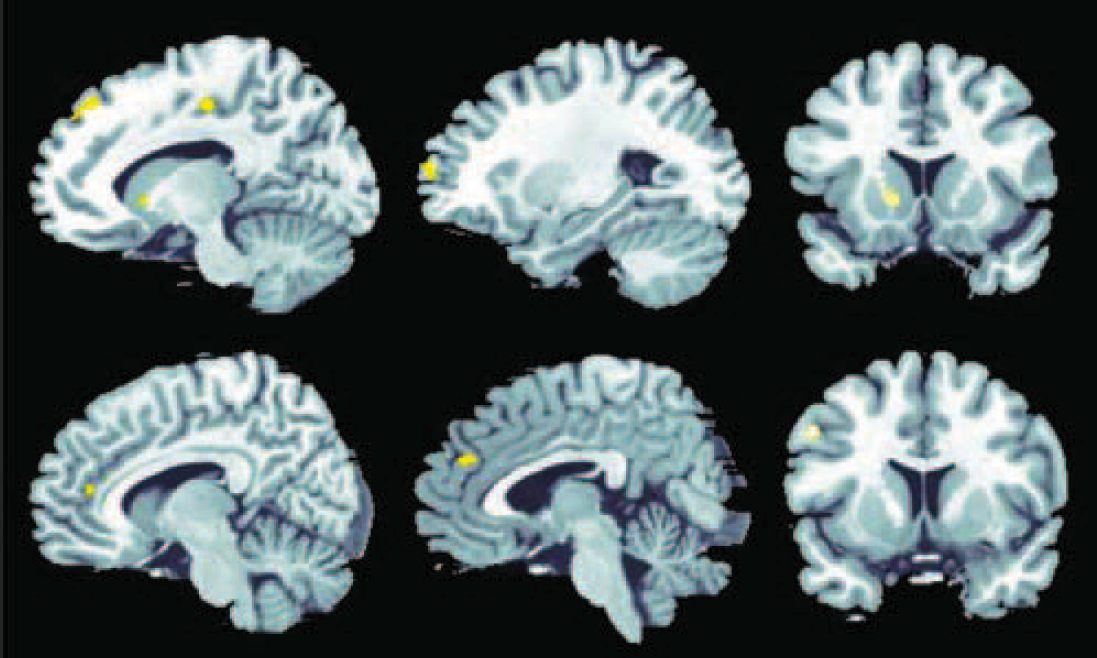

Analysis of activation in association with decision-making under maximum uncertainty yielded significant activation in the control group in an extended network containing mainly frontal, parietal and occipital regions (Fig. 2(a)). In the schizophrenia group, activation was restricted predominantly to the occipital cortex (Fig. 2(b)).

Fig. 2 Significant activation in individuals in the control group (a) and the schizophrenia group (b) in association with decision-making under uncertainty at P<0.01, false discovery rate corrected.